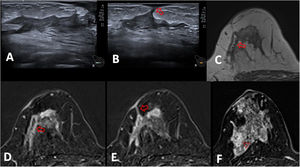

Mastitis periductal en una paciente de 26 años. A) La ecografía muestra ectasia ductal con contenido ecogénico en la mama derecha. B) Reconstrucción sagital que muestra el realce de tipo no masa de distribución segmentaria que ocupa un área de 45mm. C-E) Imagen de RM poscontraste, primera fase, T1 con saturación grasa (C) y sustracción (D), muestra la ectasia ductal con captación mural (flecha) y patrón en anillos agrupados (cabezas de flecha). E) El mapa de CDA muestra uno de los 3 valores estudiados, cuyo promedio fue 1,133×10-3mm2/s. Nótese el engrosamiento cutáneo focal hipercaptante próximo al área inflamatoria (C y D).

Mastitis granulomatosas idiopática en una paciente de 40 años. A y B) La ecografía muestra ectasia ductal con contenido ecogénico en la mama derecha, con una fístula cutánea (flecha). C) Imagen de RM en T2 que muestra las paredes del ducto engrosadas con un contenido hiperintenso (flecha). D y E) Imagen de RM poscontraste, T1 con saturación grasa y sustracción, muestran la ectasia ductal con captación mural (flecha en D) y el trayecto fistuloso a la piel (flecha en E) con engrosamiento e hipercaptación cutánea focal. F) El área inflamatoria consiste en un realce de tipo no masa de distribución segmentaria y patrón en anillos agrupados (cabeza de flecha) que ocupa un área de 45mm. El mapa de CDA mostró un promedio de 1,008×10-3mm2/s. (no mostrado).